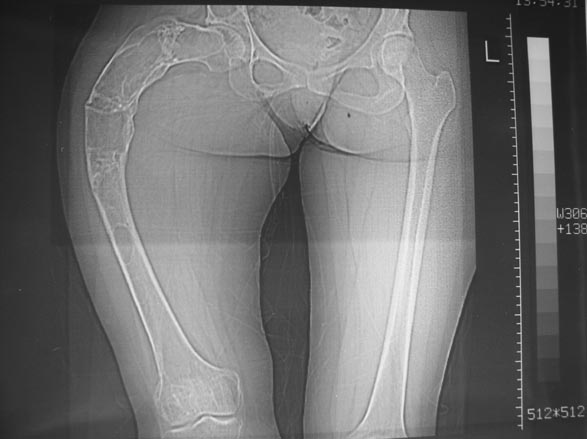

Leonid Pollyak 02 Январь 2005, 22:42

Уважаемые коллеги! С Новым годом и самых светлых пожеланий!

В ноябре этого года я обращался с просьбой о помощи в выборе тактики лечения больной с деформацией бедра на почве фиброзной дисплазии. Были получены интересные и очень полезные советы по операции.

Хотелось бы показать, что получилось в результате.

Операция выполнялась с помощью А.Н.Челнокова. Очень понравилась технология выполнения блокируемого остеосинтеза с использованием спицевого дистрактора, модифицированный гвоздь с латерализованным проксимальным отделом и возможностью многовинтовой фиксации проксимального и дистального участков бедра.

Уважаемые коллеги! Большое спасибо за живой отклик и предложения по тактике лечения. Больной произведен первый этап - стержневой аппарат издвух баз, кортикотомия, остеоклазия и начата коррекция в аппарате. Почти исправлен угол, не сегодня укорочение 2см. Когда завершим коррекция, представлю рентгенограммы.